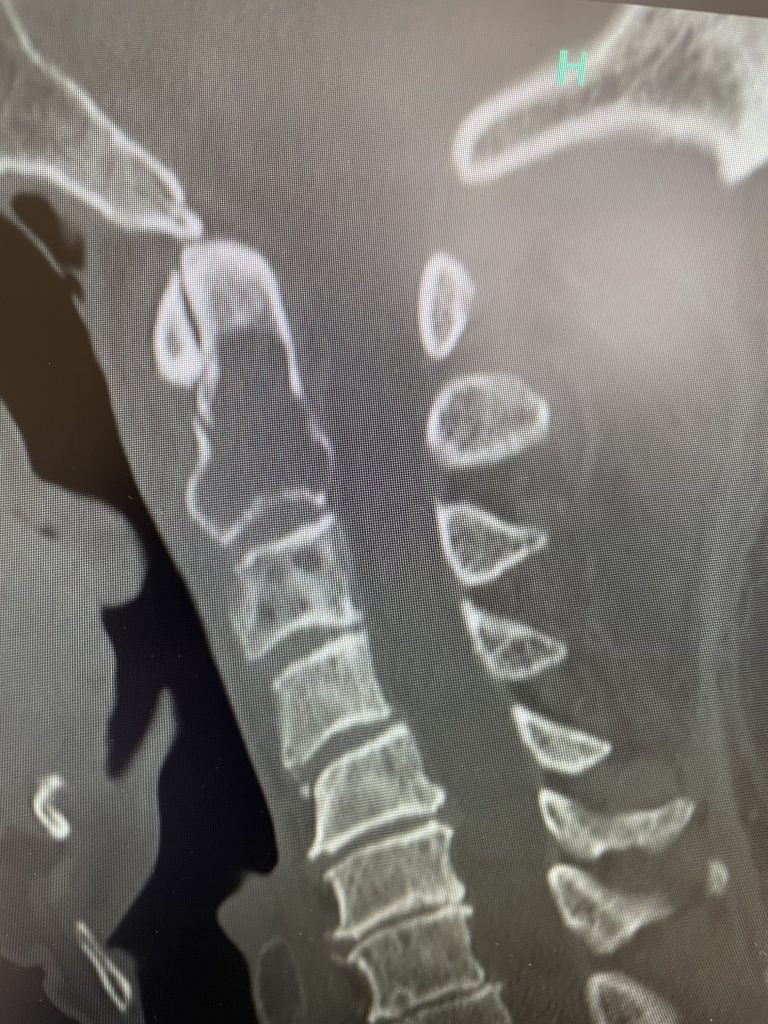

Here is a tough case: This is a 72 year-old male who presented with several months of progressive neck pain without symptoms of the arms or legs. […]